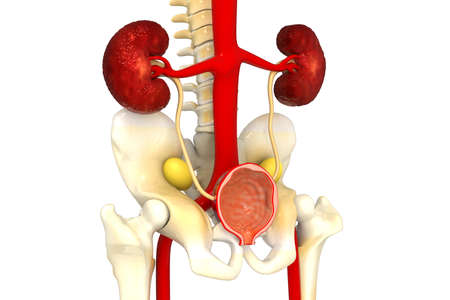

Digital illustration of pelvic girdle in colour background 3D illustration of Human Urinary System Anatomy